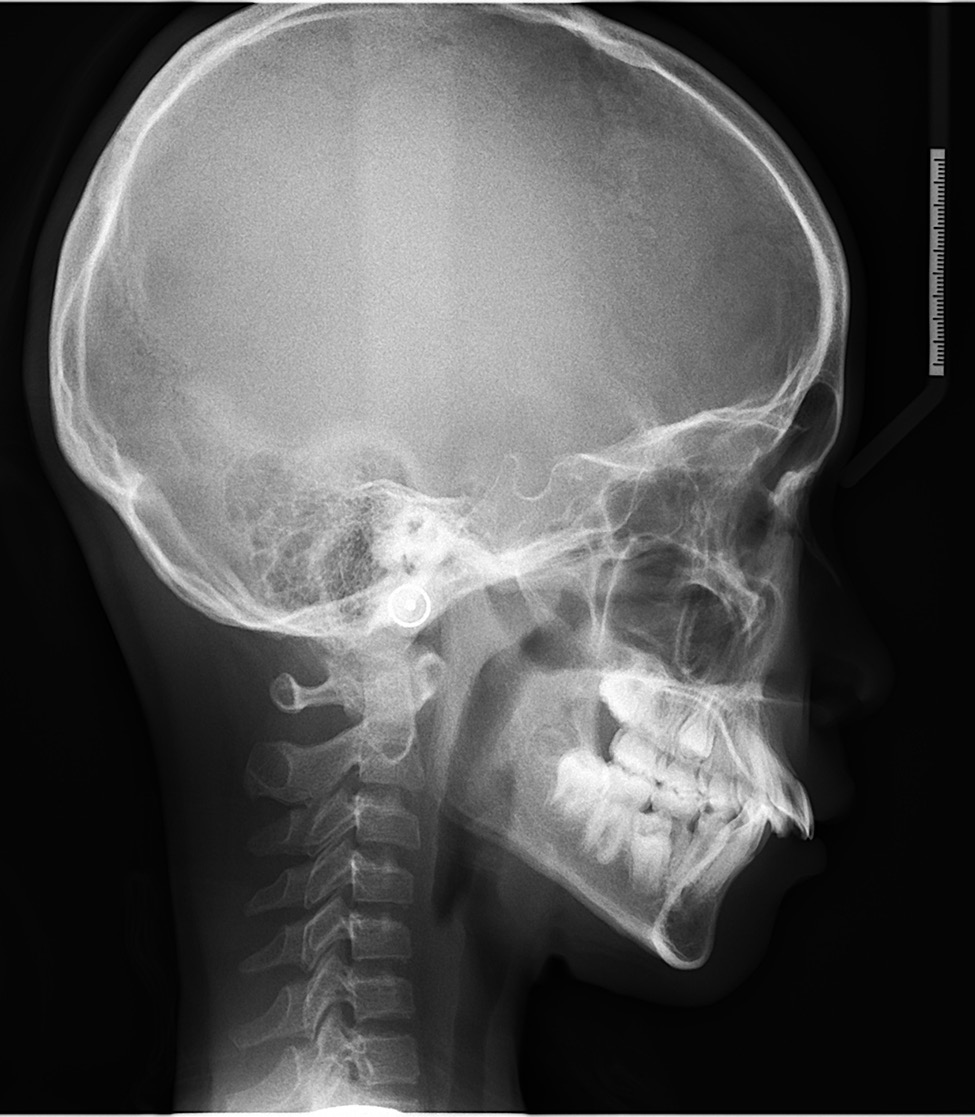

这位小朋友主诉牙不齐,嘴突,没下巴,来面诊时刚刚结束替牙期,正处于年轻恒牙列,生长发育高峰期。

根据牙片资料和口内检查发现骨性,上前牙唇倾,lll度深覆盖,上下颌牙弓狭窄,右下4左下5先天缺失,上颌轻度拥挤,下颌牙齿散在间隙,颏唇沟较深,闭唇时颏肌紧张。

从牙片资料看上下前牙内收直立,颌平面整平,上颌内收,前牙达到正常覆合覆盖,颏部前伸良好。